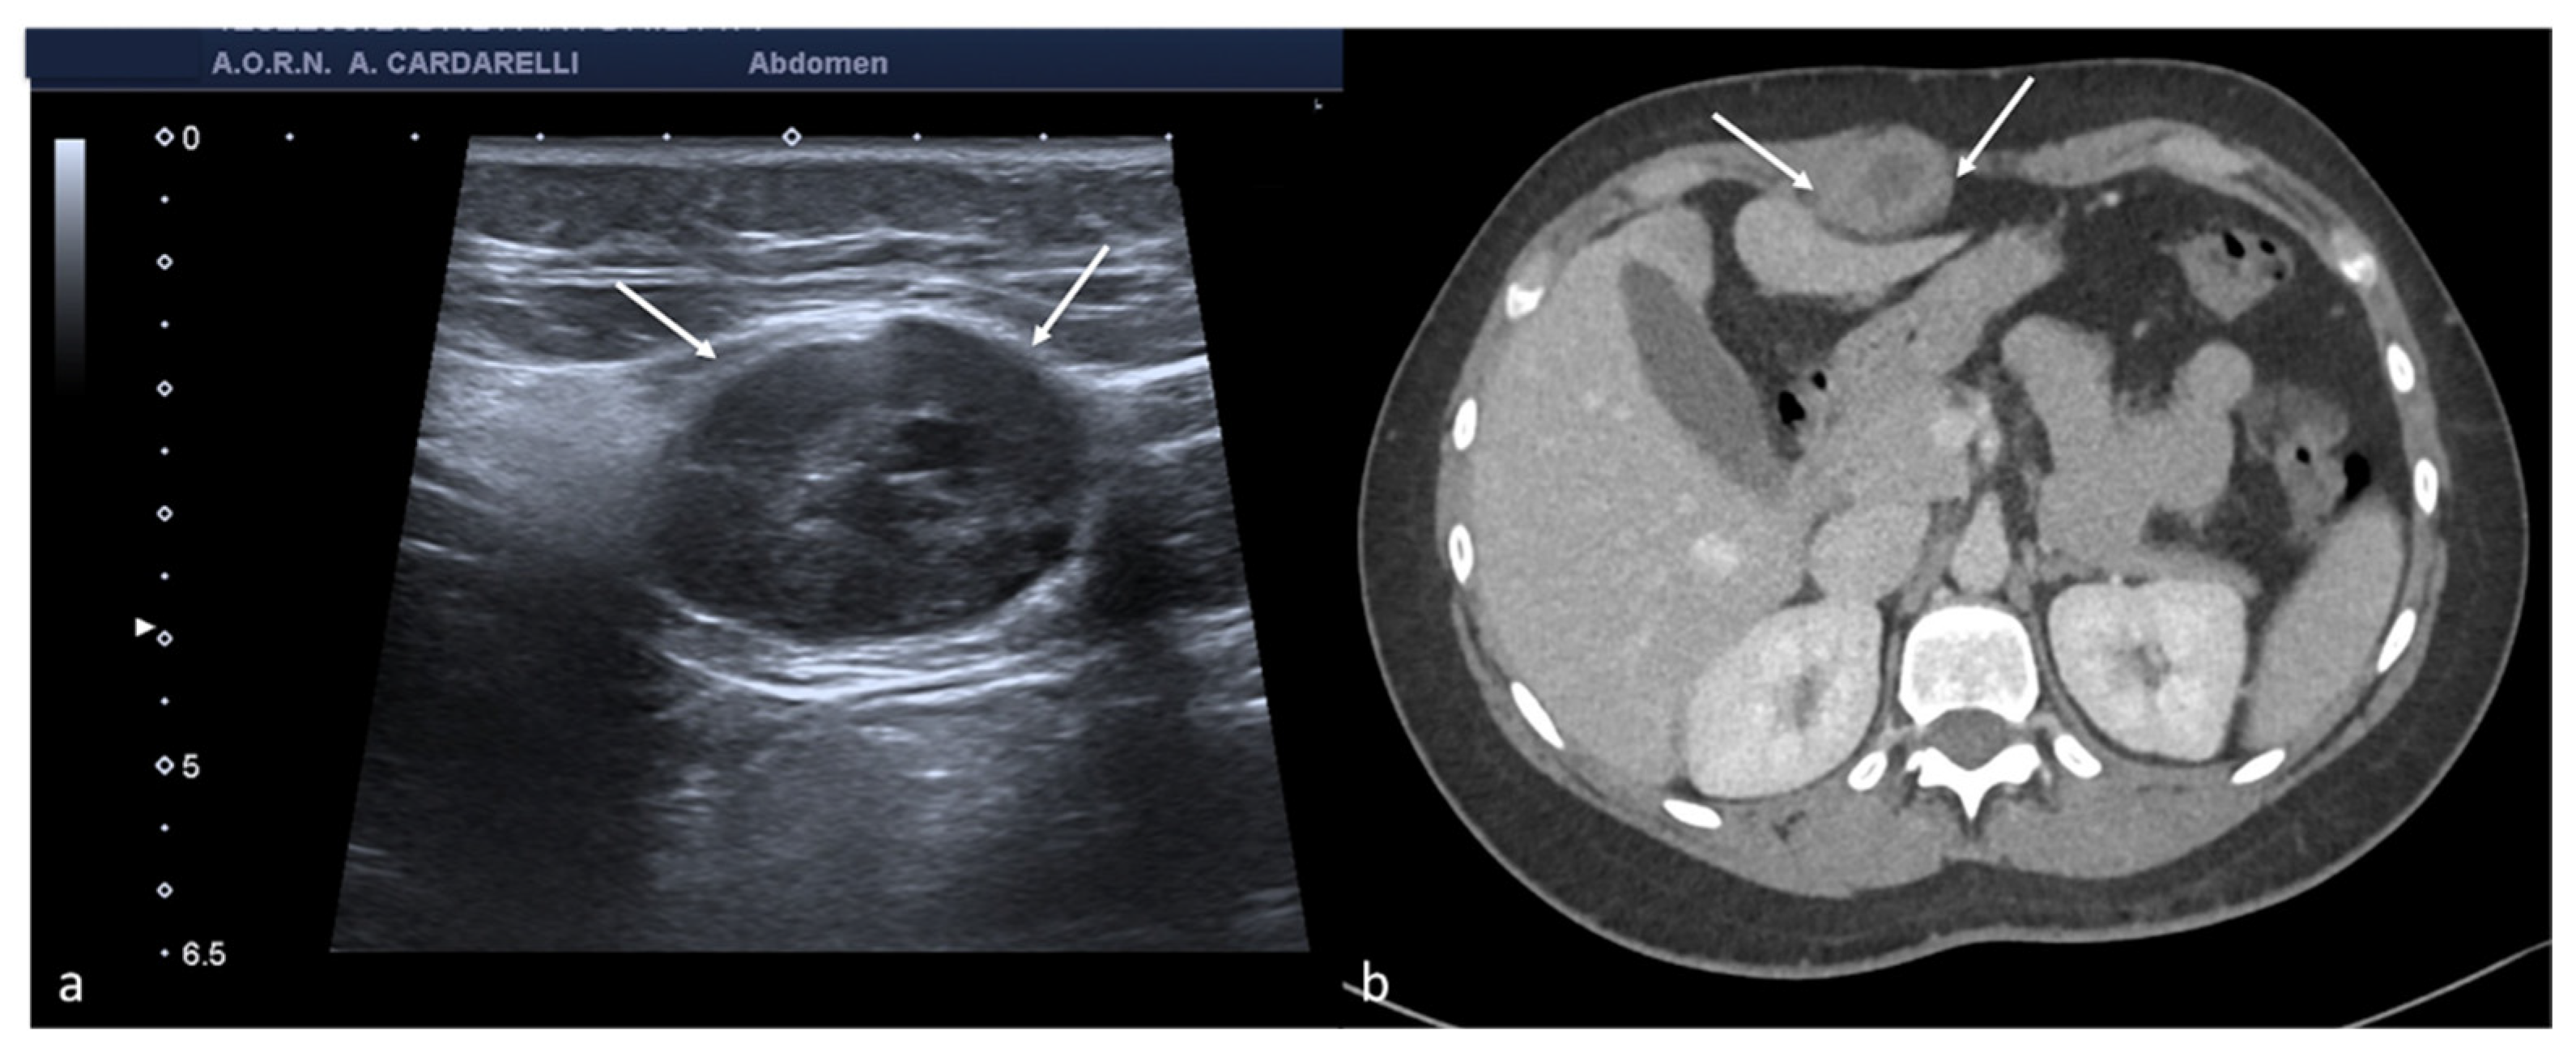

Figure 9. Abdominal wall endometriosis nodule. TSA–US axial scan (a) of the abdominal wall shows a 35 mm abdominal wall endometriosis nodule with hypoechoic content and well-defined margins ((a), arrows). The nodule is enclosed in the muscular fascia along the right rectal abdomen. Contrast-enhanced axial CT image (b) shows heterogeneous enhanced mass in the right rectus sheath. The mass was subsequently proved to be abdominal endometriosis.